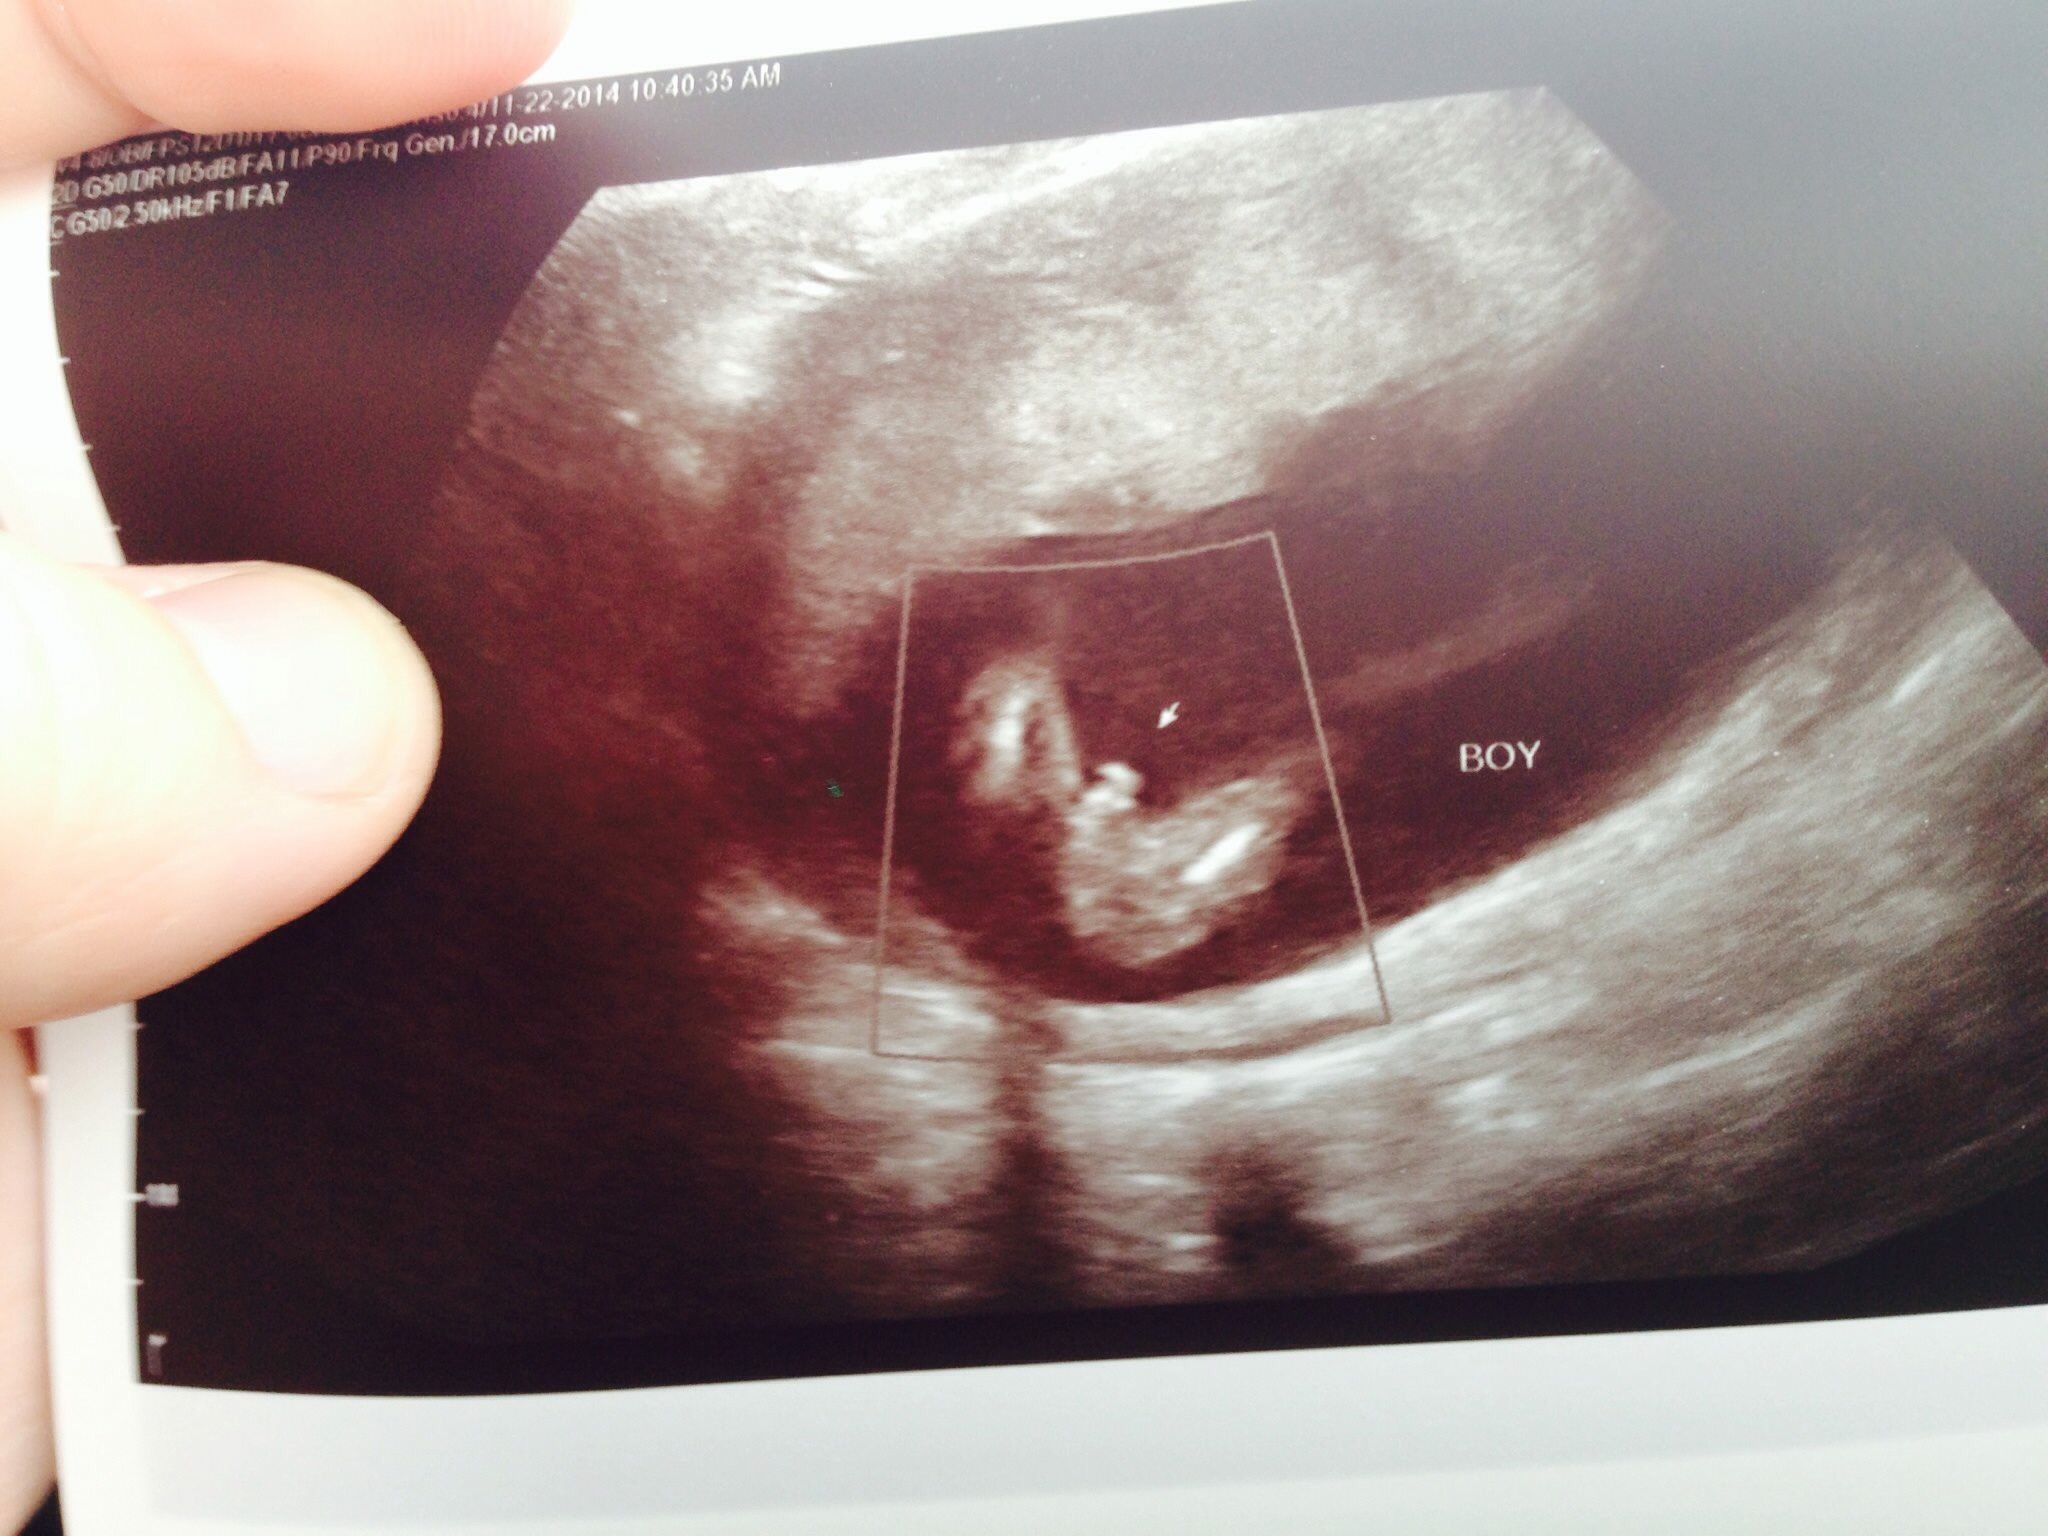

So yesterday went to see midwife and told her I had a private scan at 15wk as had some pain and they could fit me in the same day. Showed her the potty shot and she said guessing you were told boy? So i said yeah and ive started my shopping and she then said I wouldnt go too mad as I have seen girl ultrasounds at 15wk 0d that could look like that as there doesnt seem to be a definite willy it could well be swollen girls bits......cue acting fine in the room.....leave the room huge panic what do I do if she is right with all the stuff Ive bought :omg:

I have only had a girl before so cant say I know a lot about looking at boys bits on ultrasounds